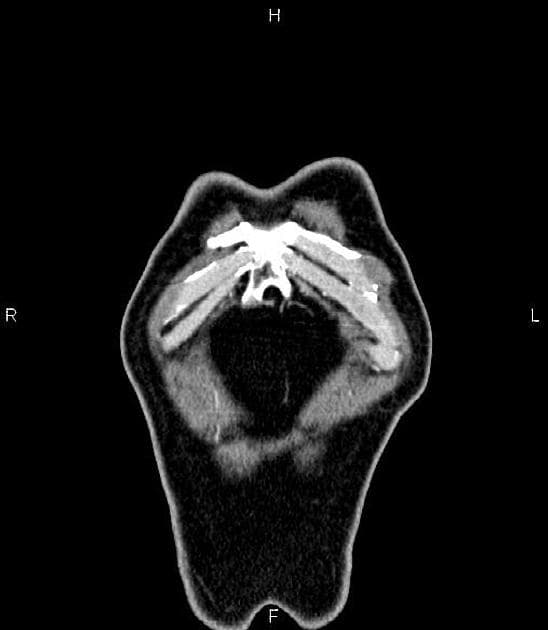

- Có giãn dạng thoi các ống mật ngoài gan (bao gồm ống mật chủ và ống gan chung) chứa nhiều ổ giảm tín hiệu trên mọi chuỗi xung, phân bố theo trọng lực, phù hợp với hình ảnh sỏi.

Interpretation: U nang ống mật chủ (type 1) kèm theo tổn thương IPMN nhánh bên phát hiện tình cờ (incidental side branch IPMN).

U nang ống mật chủ - type I (choledochal cyst - type I)